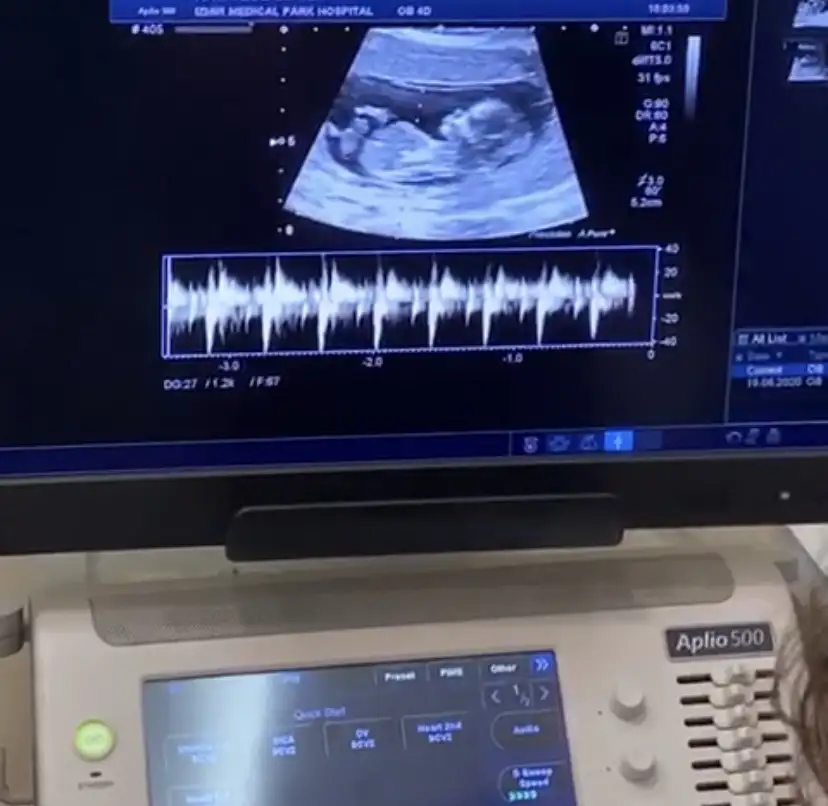

Merhaba cinsiyeti nedir sizce